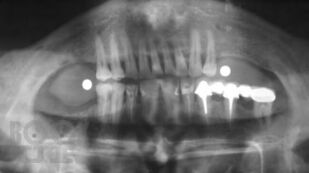

Основы дентальной имплантологии

В учебном пособии освещены основные хирургические и ортопедические вопросы дентальной имплантации.

Пособие предназначено для студентов стоматологических факультетов медицинских вузов, для интернов и клинических ординаторов, которые собираются стать врачами хирургами-имплантологами, а также для инженеров и ученых, занимающихся разработкой дентальных имплантатов. Книга будет также интересна широкому кругу читателей, интересующихся этой темой.